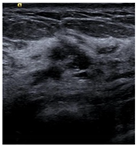

| Negative | Image | ![]() | ![]() | ![]() | ![]() |

| Number | 98 | 112 | 345 | 289 | |

| Positive | Image | ![]() | ![]() | ![]() | ![]() |

| Number | 47 | 49 | 161 | 184 | |